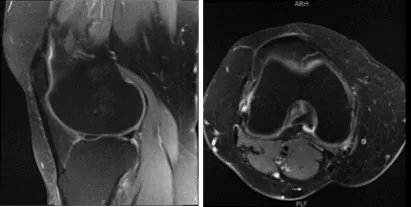

The patient presented an MRI result that showed undersurface tear of the medial meniscal body resulting in a small peripheral meniscal flap. Small radial tear at the free edge of the lateral meniscal body. Mild to moderate cartilage loss in the medial compartment and a small joint effusion.

MRI-3T Knee non-contrast